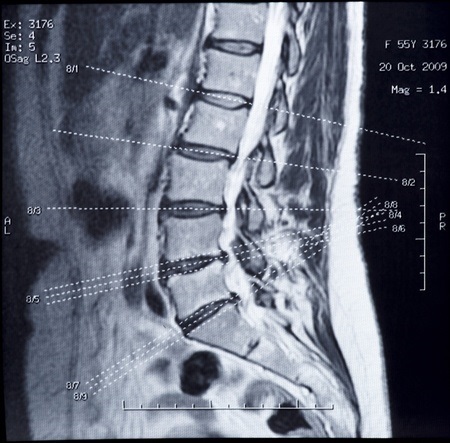

「レントゲン、MRI検査で原因がわかり、適切な処置が受けられる…」 と思われますが、あなたの訴える症状が検査結果に現れるとは限りません。

この整形外科のドクターも検査にはまったく異常がありませんでした。